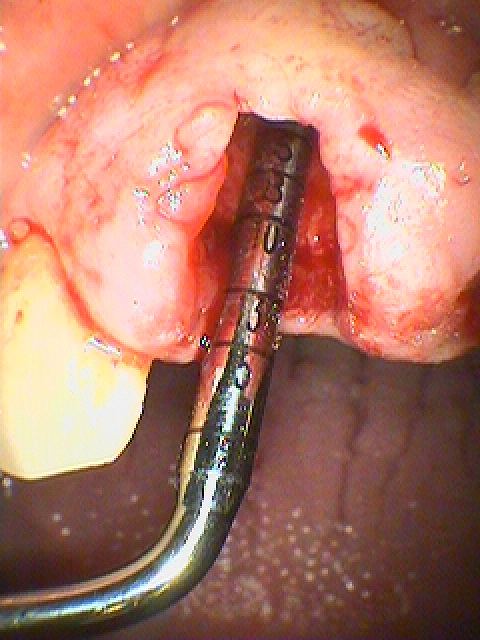

歯茎から膿が大量に出てきています

消炎処置後、腫れが引いてみていきます

歯が割れてきていました

骨補填材を転入し、ソケットプリザベーションを一応行っていきました

今回はアパタイト顆粒を転入しています